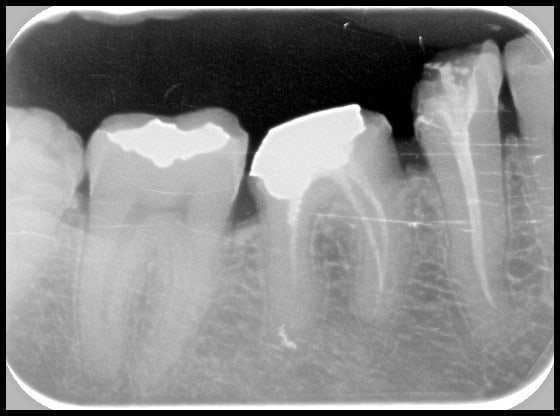

(Des fois l'endo ça marche. Protaper + Gutta condensor)

Reste plus qu'à faire la même sur tous mes cas...

R5 ngbr3g - Eugenol